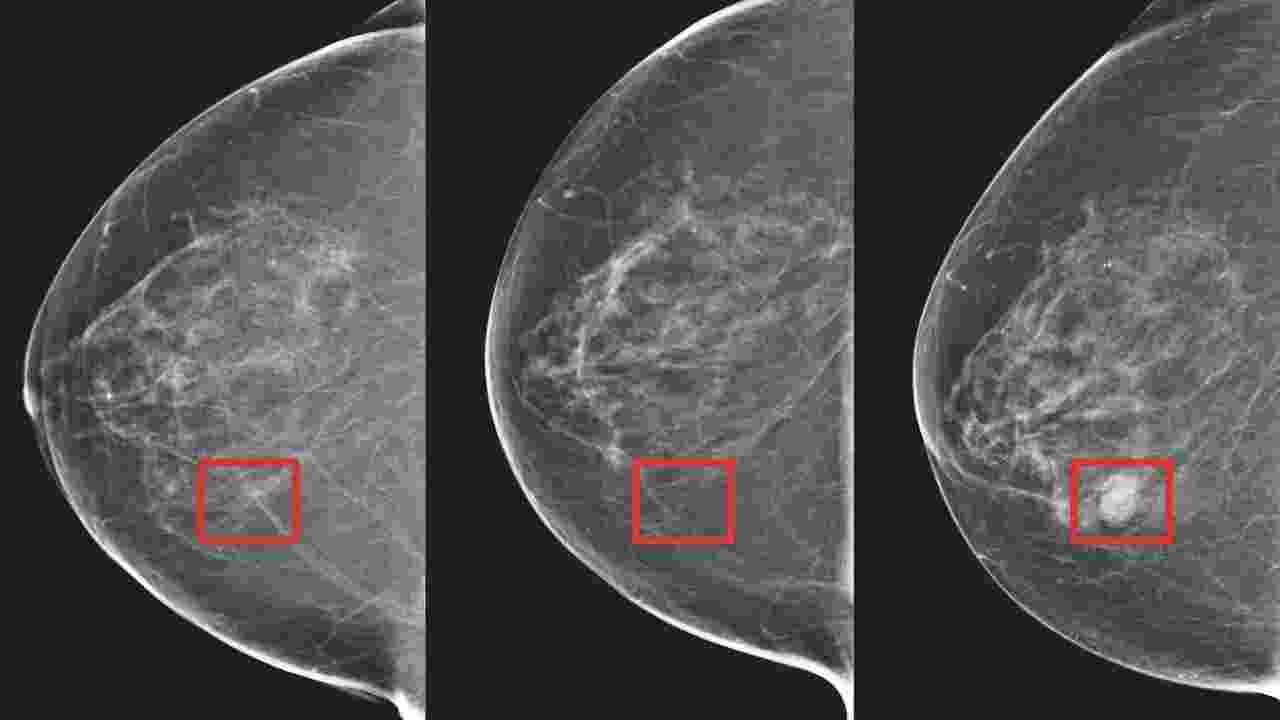

A new machine learning-based tool is 98 percent effective in identifying early signs of breast cancer, as reported in a study.